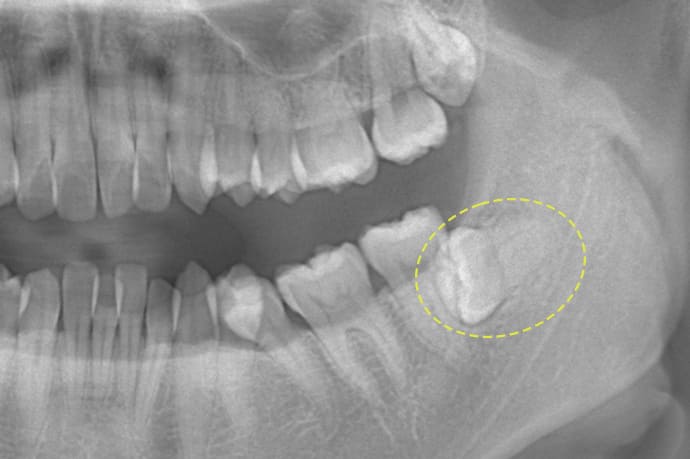

水平埋伏の親知らず - 難易度:難

歯茎の中で完全に横向きに生えているタイプの親知らずは、水平埋伏智歯と呼ばれます。このタイプは主に下顎にみられます。真横に生えているため、抜歯の際には難易度が高く、通常は歯を2~3つに分割して除去を行います。